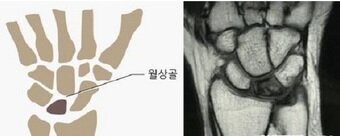

손목 희귀질환 키엔벡병, 조기진단이 중요하다

키엔벡병 MRI ⓒ 뉴스1